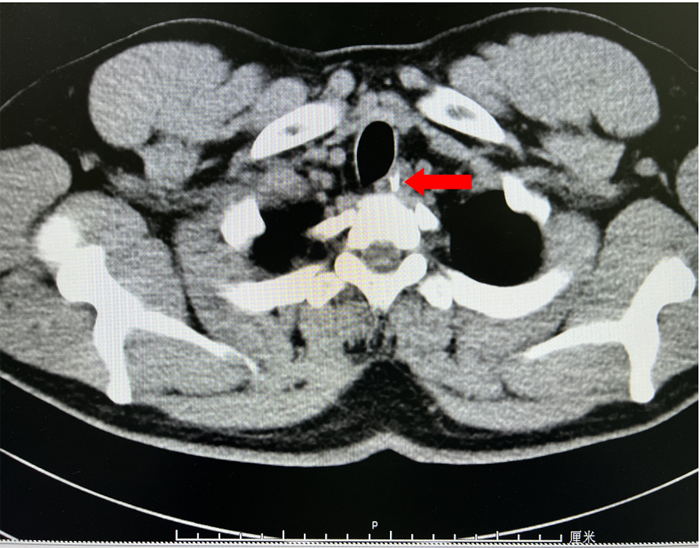

為了解魚刺與周圍的關(guān)系及是否刺入血管,患者入院后給予完善胸部強化CT,示胸上段管腔內(nèi)高密度影,考慮食管異物。李曙暉主任醫(yī)師結(jié)合患者病史、2次胃鏡結(jié)果及胸部CT等,分析認為魚刺已深深扎入食管壁內(nèi),可行食管黏膜剝離術(shù)暴露出異物后再行取出。12月28日,李曙暉主任醫(yī)師在麻醉和護理團隊的配合下行胃鏡檢查,內(nèi)鏡下距門齒18cm可見食管黏膜充血水腫,未見異物,遂用黏膜切開刀切開周圍黏膜及肌層,暴露出異物頂端,再用鱷口鉗鉗住魚刺頂端,順利取出一枚長3cm多的魚刺,看到大部分魚刺扎入食管壁。術(shù)后對癥治療后,患者現(xiàn)已痊愈出院。

CT紅色箭頭所示異物